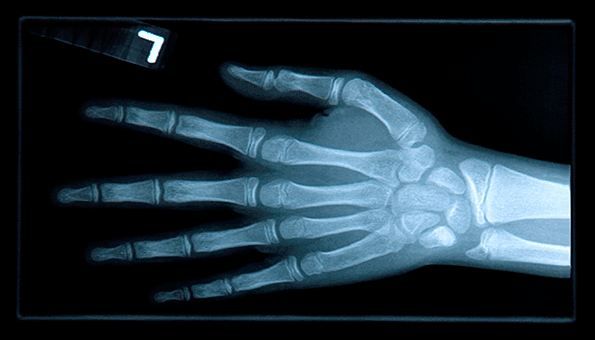

A hydraulic press crushed a 62-year-old machine operator’s left hand at a seal and gasket manufacturer in New Philadelphia, Ohio, resulting in multiple broken bones. The injured employee, who had worked at the Lauren Manufacturing for 15 years, has been unable to return to work and has endured three surgeries as a result.